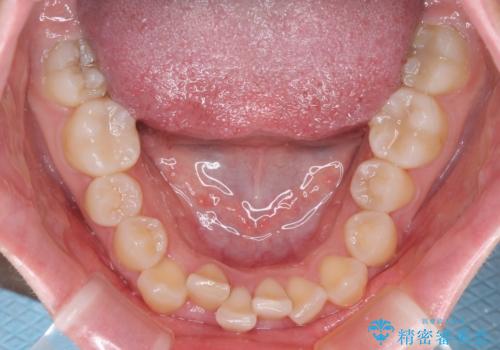

- 上顎の八重歯と、上下前歯のデコボコを気にして来院された患者様です。

奥歯の咬み合わせを見ると、上顎臼歯が下顎に対して前方にあり、叢生改善により口元が突出する顔貌ではなかったため、上顎左右第一小臼歯2本を抜歯し、ワイヤー装置にて矯正治療を行うこととしました。

前歯部のデコボコがなくなったため、歯磨きしやすくなり、非常に清潔な状態になりました。